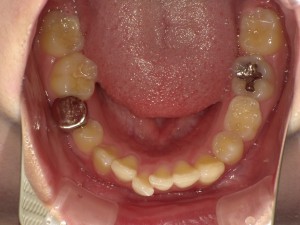

装置装着!!

こんにちは!先月矯正を始めた吉田です。

今月の矯正日ではついに装置を付けました! 入れて少しすると痛みがでてきましたが、

痛みどめを飲んだらだいぶ落ち着いてきました。

口蓋にぴったりレジンでできた板食い込んでいたかったのですが2,3日で慣れていきました。

口蓋の痛みよりも歯の移動に伴う痛みのほうがすごかったです。

3週間ぐらいたった今では慣れてきて痛みは感じなくなりましたが、最初は涙が出そうになるくらいでした

そして、装置入れてしばらくたってから、歯の数を上と下とをそろえるために、今回上の永久歯を左右一本づつ抜きました!

下の歯も抜くことになっていますがいつ抜くかは指示待ちです。

今回の写真では装置入れたときのみの写真になっていますが、来月の写真ではちゃんと

上が歯抜け状態になっていますので、比べてみてください!

装置入れたことで奥歯が磨きにくくなりましたが、汚れがたまらないように毎日念入りに磨いてます♪